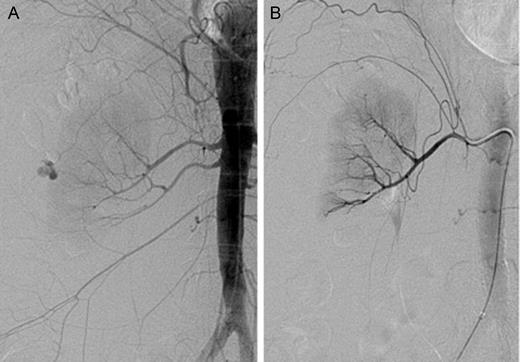

An emergent renal angiogram revealed two right renal arteries with active contrast extravasation from the subsegmental branch of the superior right renal artery (Fig. 2A). This was successfully embolized (Fig. 2B). This case was clinically diagnosed as a spontaneous retroperitoneal hemorrhage with subcapsular hematoma, otherwise known as WS.

Identification and subsequent embolization of an active extravasation from the superior right renal artery. (A) Renal angiogram of the right kidney prior to embolization. Both a superior and an inferior right renal arteries are present. There is an active extravasation of blood from the subsegmental branch of the superior right renal artery. (B) Post-embolization renal angiogram. There is no definitive focus of active extravasation